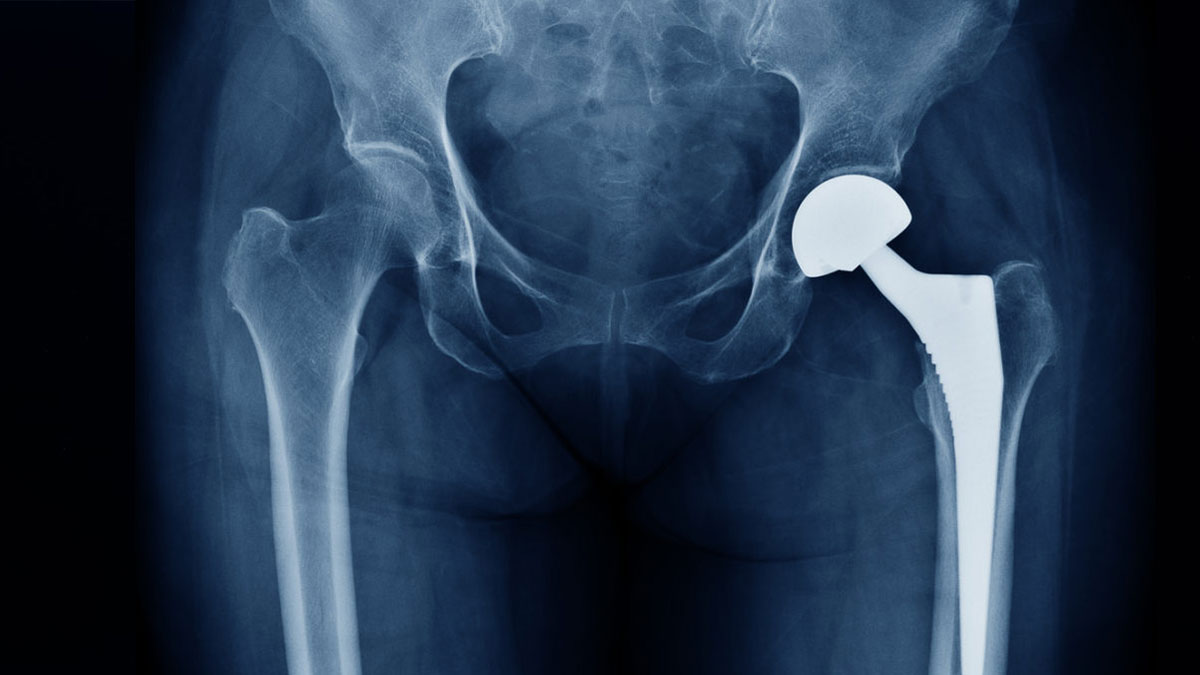

हड्डी टूटना (फ्रैक्चर) एक आम समस्या है। कुछ मामलों में सर्जरी के दौरान प्लेट, स्क्रू या रॉड (मेटल इंप्लांट) लगाना जरूरी हो जाता है, लेकिन हर फ्रैक्चर के इलाज में मेटल इंप्लांट की जरूरत नहीं होती। कई बार हड्डी को बिना ऑपरेशन के भी ठीक किया जा सकता है। मेटल इंप्लांट का इस्तेमाल हड्डी को सही स्थिति में रखने, जल्दी जुड़ने और दोबारा चोट से बचाने के लिए किया जाता है। डॉक्टर यह फैसला हड्डी की स्थिति, चोट की गंभीरता, उम्र और स्वास्थ्य स्थिति को देखकर करते हैं। अगर समय पर सही इलाज न मिले, तो हड्डी गलत जुड़ सकती है, जिसके कारण दर्द या चलने-फिरने में दिक्कत आ सकती है। इसलिए यह जानना जरूरी है कि हड्डी टूटने पर मेटल इंप्लांट की जरूरत कब पड़ती है। इस विषय पर बेहतर जानकारी के लिए हमने लखनऊ के अपोलो हॉस्पिटल के ऑर्थो डिपार्टमेंट के आर्थोपेडिक सर्जन डॉ इमरान अख्तर से बात की।

जब बोन फ्रैक्चर होने पर हड्डी कई टुकड़ों में टूट जाती है या हड्डी जगह से हट जाती है, तो सिर्फ प्लास्टर या ब्रेस से ठीक होना मुश्किल होता है। ऐसे मामलों में प्लेट या रॉड जैसी मेटल इंप्लांट लगाए जाते हैं, ताकि हड्डी स्थिर रहे और सही ढंग से जुड़ सके।

पैर, जांघ, टखना या पेल्विस जैसी हड्डियां वजन सहने वाली होती हैं। इन पर दबाव ज्यादा होता है, इसलिए इनकी चोट के बाद इंप्लांट लगाने से जल्दी रिकवरी होती है और दोबारा चोट लगने का खतरा कम होता है।

घुटना, कोहनी, कंधा या कलाई जैसी जगहों के पास की हड्डियां अगर टूट जाएं, तो उनकी स्थिति और मूवमेंट बनाए रखना मुश्किल हो जात होता है। ऐसे फ्रैक्चर में मेटल इंप्लांट लगाकर हड्डी को स्थिर किया जाता है ताकि बाद में जोड़ों की मूवमेंट में दिक्कत न हो।